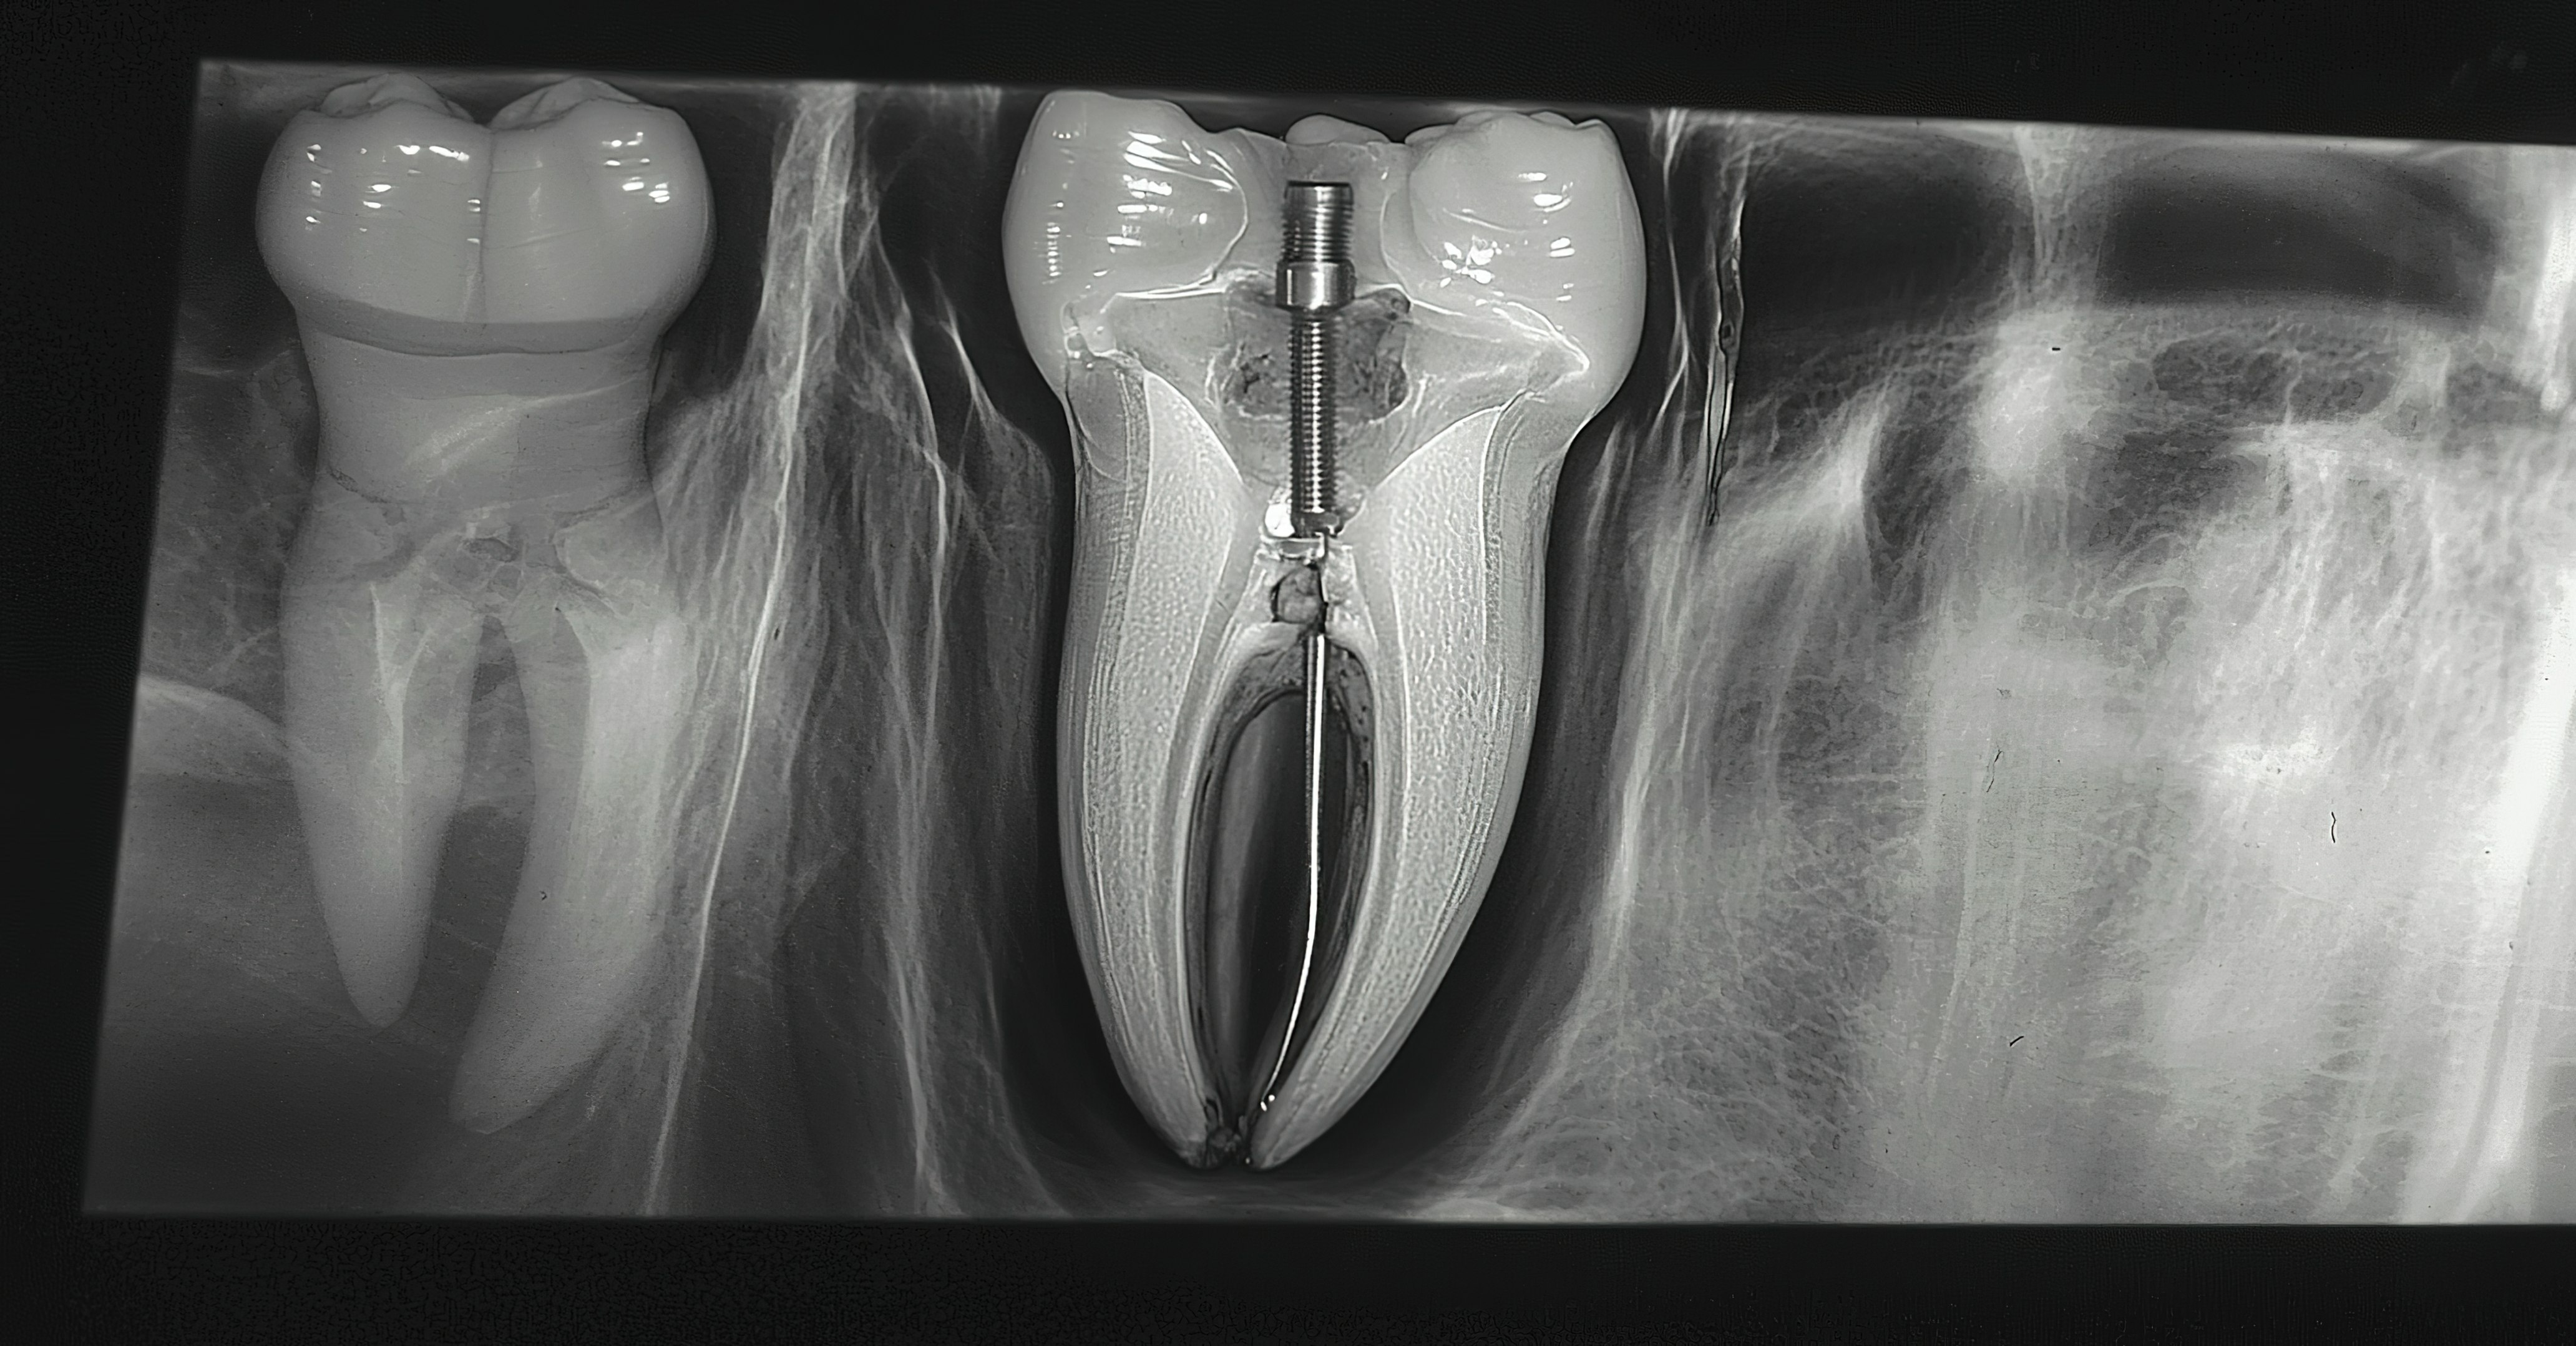

To investigate the feasibility of using an AR headset displaying a guide system for post removal, 50 maxillary first molars were implanted into a 3D-printed jaw and divided into an AR HMD plus DNS group (n=25) and a DNS group (n=25).

Palatal canals were restored with fiber posts and a core buildup was done. Additionally, cone-beam computed tomography scans were taken before and after posts were removed, and the drilling course and depth were planned in the navigation system. Global coronal deviation, global apical deviation, and angular deflection were measured, and the number of mishaps were recorded, according to the study.

Compared to the navigation system alone, the AR HMD plus DNS revealed significantly lower 3D global coronal, global apical, and angular deflection deviations below 1 mm when removing posts from molars, the authors wrote.